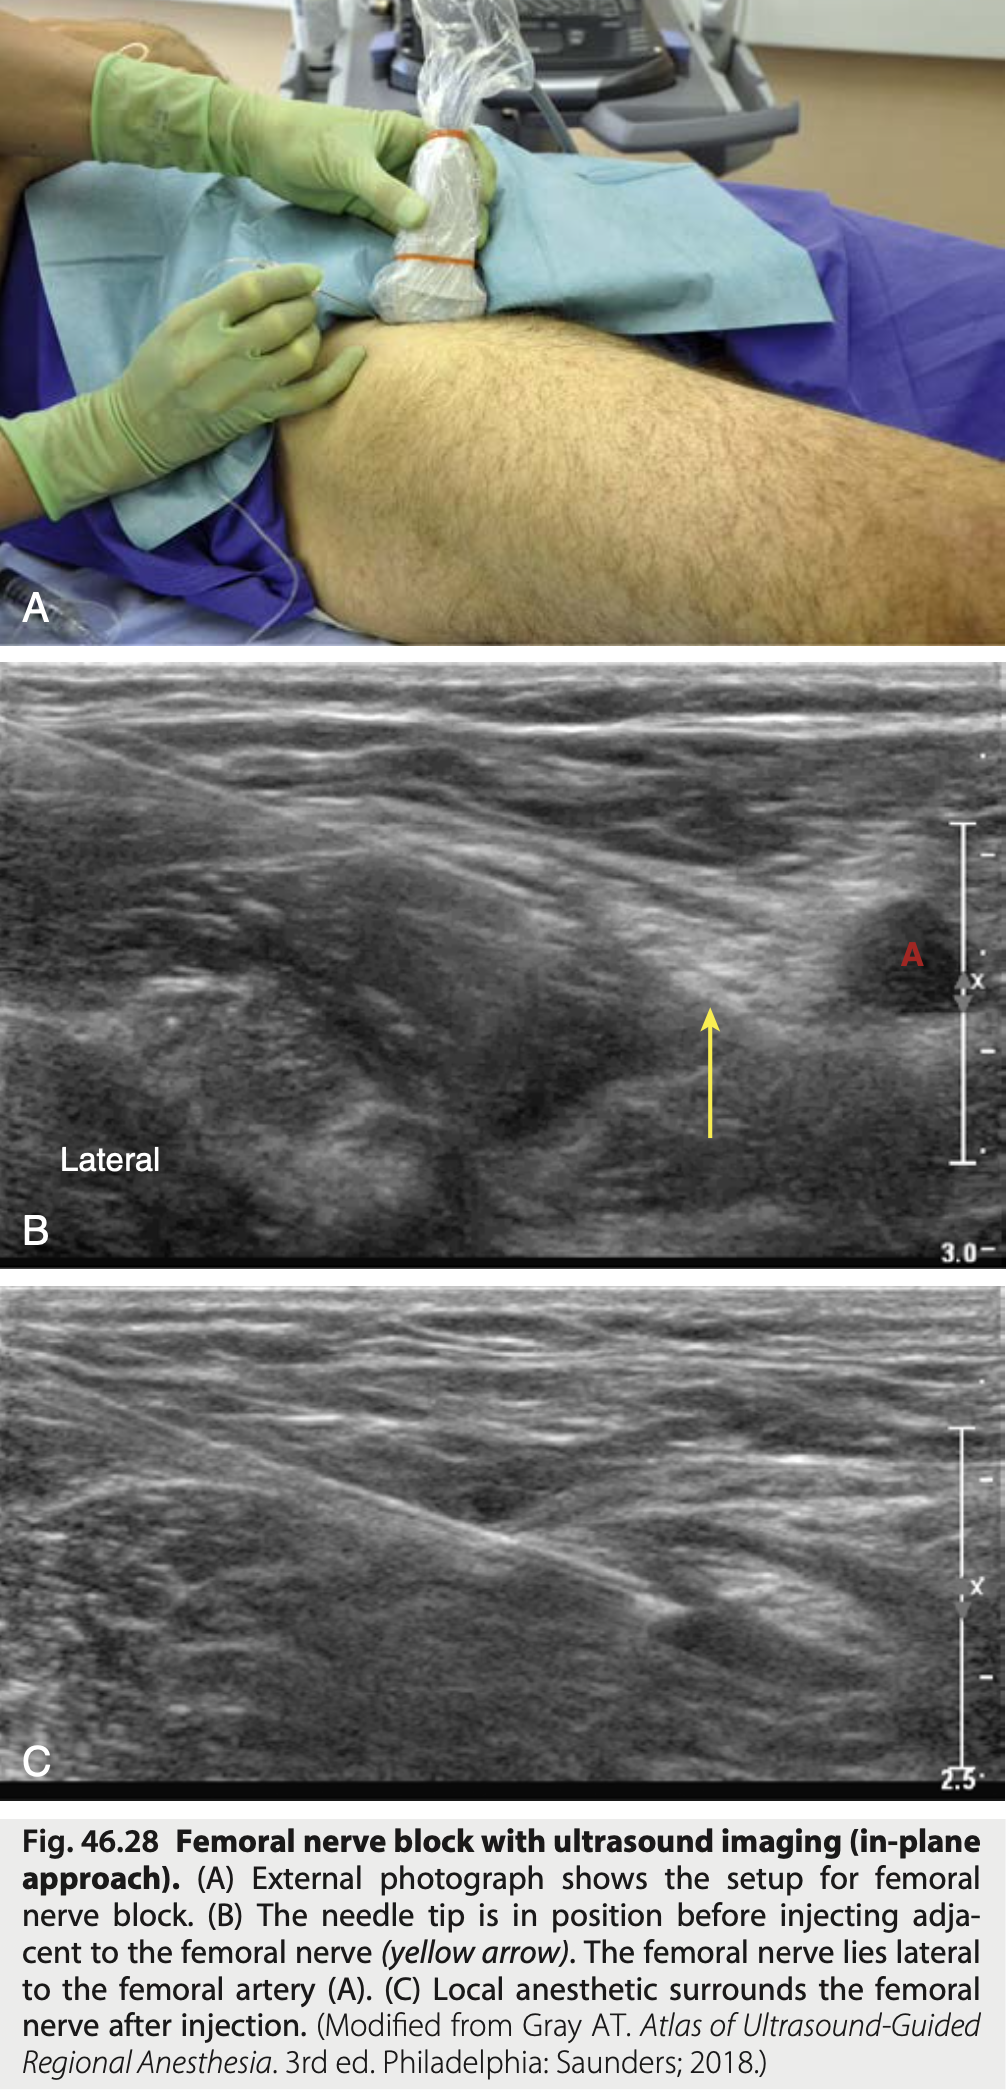

Qual o bloqueio conforme a figura?

Bloqueio femoral

Identificar as estruturas conforme a imagem do bloqueio femoral

* Agulha vem lateralmente e sente a resistencia das duas fascias ("duplo-click") * 10-15ml AL

Quais regiões afetadas pelo bloqueio femoral * sensitivo * motor * osseo

28

Indicacoes do bloqueio femoral

* Quadril * Coxa * Joelho

29

Efeitos colaterais de bloqueio femoral

Fraqueza quadriceps